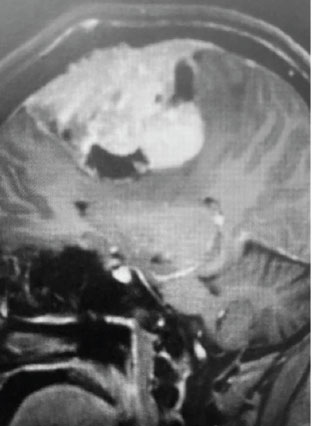

Fig 1. A) Pre-operative, post-contrast, coronal MRI. Arrow points to tumor involvement in the superior sagittal sinus.

This is a 55 year old right-handed woman who was having progressive balance problems. MRI with and without contrast demonstrated a 7 cm partly cystic meningioma involving the left frontal convexity and falx, and encasing the superior sagittal sinus. There was also tumor involvement of part of the convexity skull.

Meningiomas that involve the superior sagittal sinus: Sometimes convexity or falx meningiomas will grow into the superior sagittal sinus. Sometimes the sinus can become completely occluded. Usually this occurs over many years, and as such, the brain has time to develop venous collaterals. So, while in a normal person, sudden occlusion of the superior sagittal sinus could lead to venous infarction or death, the very gradual occlusion that can be seen with meningiomas, does not lead to these problems. Also, if the sinus is filled with tumor and completely occluded, it can usually be safely removed at that segment.